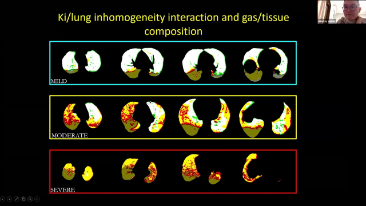

A escolha das configura??es corretas do respirador para o tratamento de pacientes com doen?as do trato respiratĂłrio Ă© uma quest?o muito importante. Como a tarefa de especificar os par?metros do equipamento de ventila??o Ă© inteiramente realizada por um mĂ©dico, o conhecimento e a experiĂȘncia do mĂ©dico na sele??o desses par?metros tem um efeito direto na precis?o de suas decis?es. O paradigma do atendimento de apoio aos pacientes mudou significativamente ao longo dos Ășltimos 20 anos. Atualmente, vĂĄrios modos de ventila??o e ferramentas de apoio Ă decis?o foram desenvolvidos em torno das necessidades clĂnicas para ajudar os profissionais clĂnicos a melhorar a eficiĂȘncia e eliminar os erros nas decis?es clĂnicas.

Integrando oxigenoterapia de alto fluxo, ventila??o n?o invasiva e ventila??o invasiva, os respiradores 3 em 1 da sĂ©rie SV reĂșnem desempenho estĂĄvel, fun??es versĂĄteis e facilidade de uso. Os recursos excepcionais de prote??o pulmonar e as vĂĄrias ferramentas de apoio Ă tomada de decis?es dos respiradores s?o projetados para diminuir o risco de infec??es cruzadas e facilitar a rotina diĂĄria dos profissionais clĂnicos.